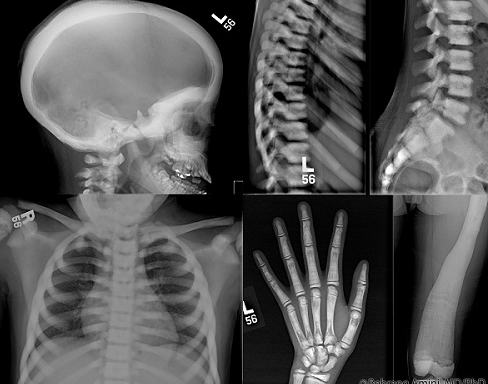

Việc chẩn đoán thường dựa vào kiểm tra sức khỏe tổng quát và chụp X – quang. Hình ảnh X – quang sẽ cho thấy mật độ xương dày hơn mức bình thường và cấu trúc xương đặc không có tủy xương. Các xét nghiệm di truyền cũng có thể giúp chẩn đoán căn bệnh này.